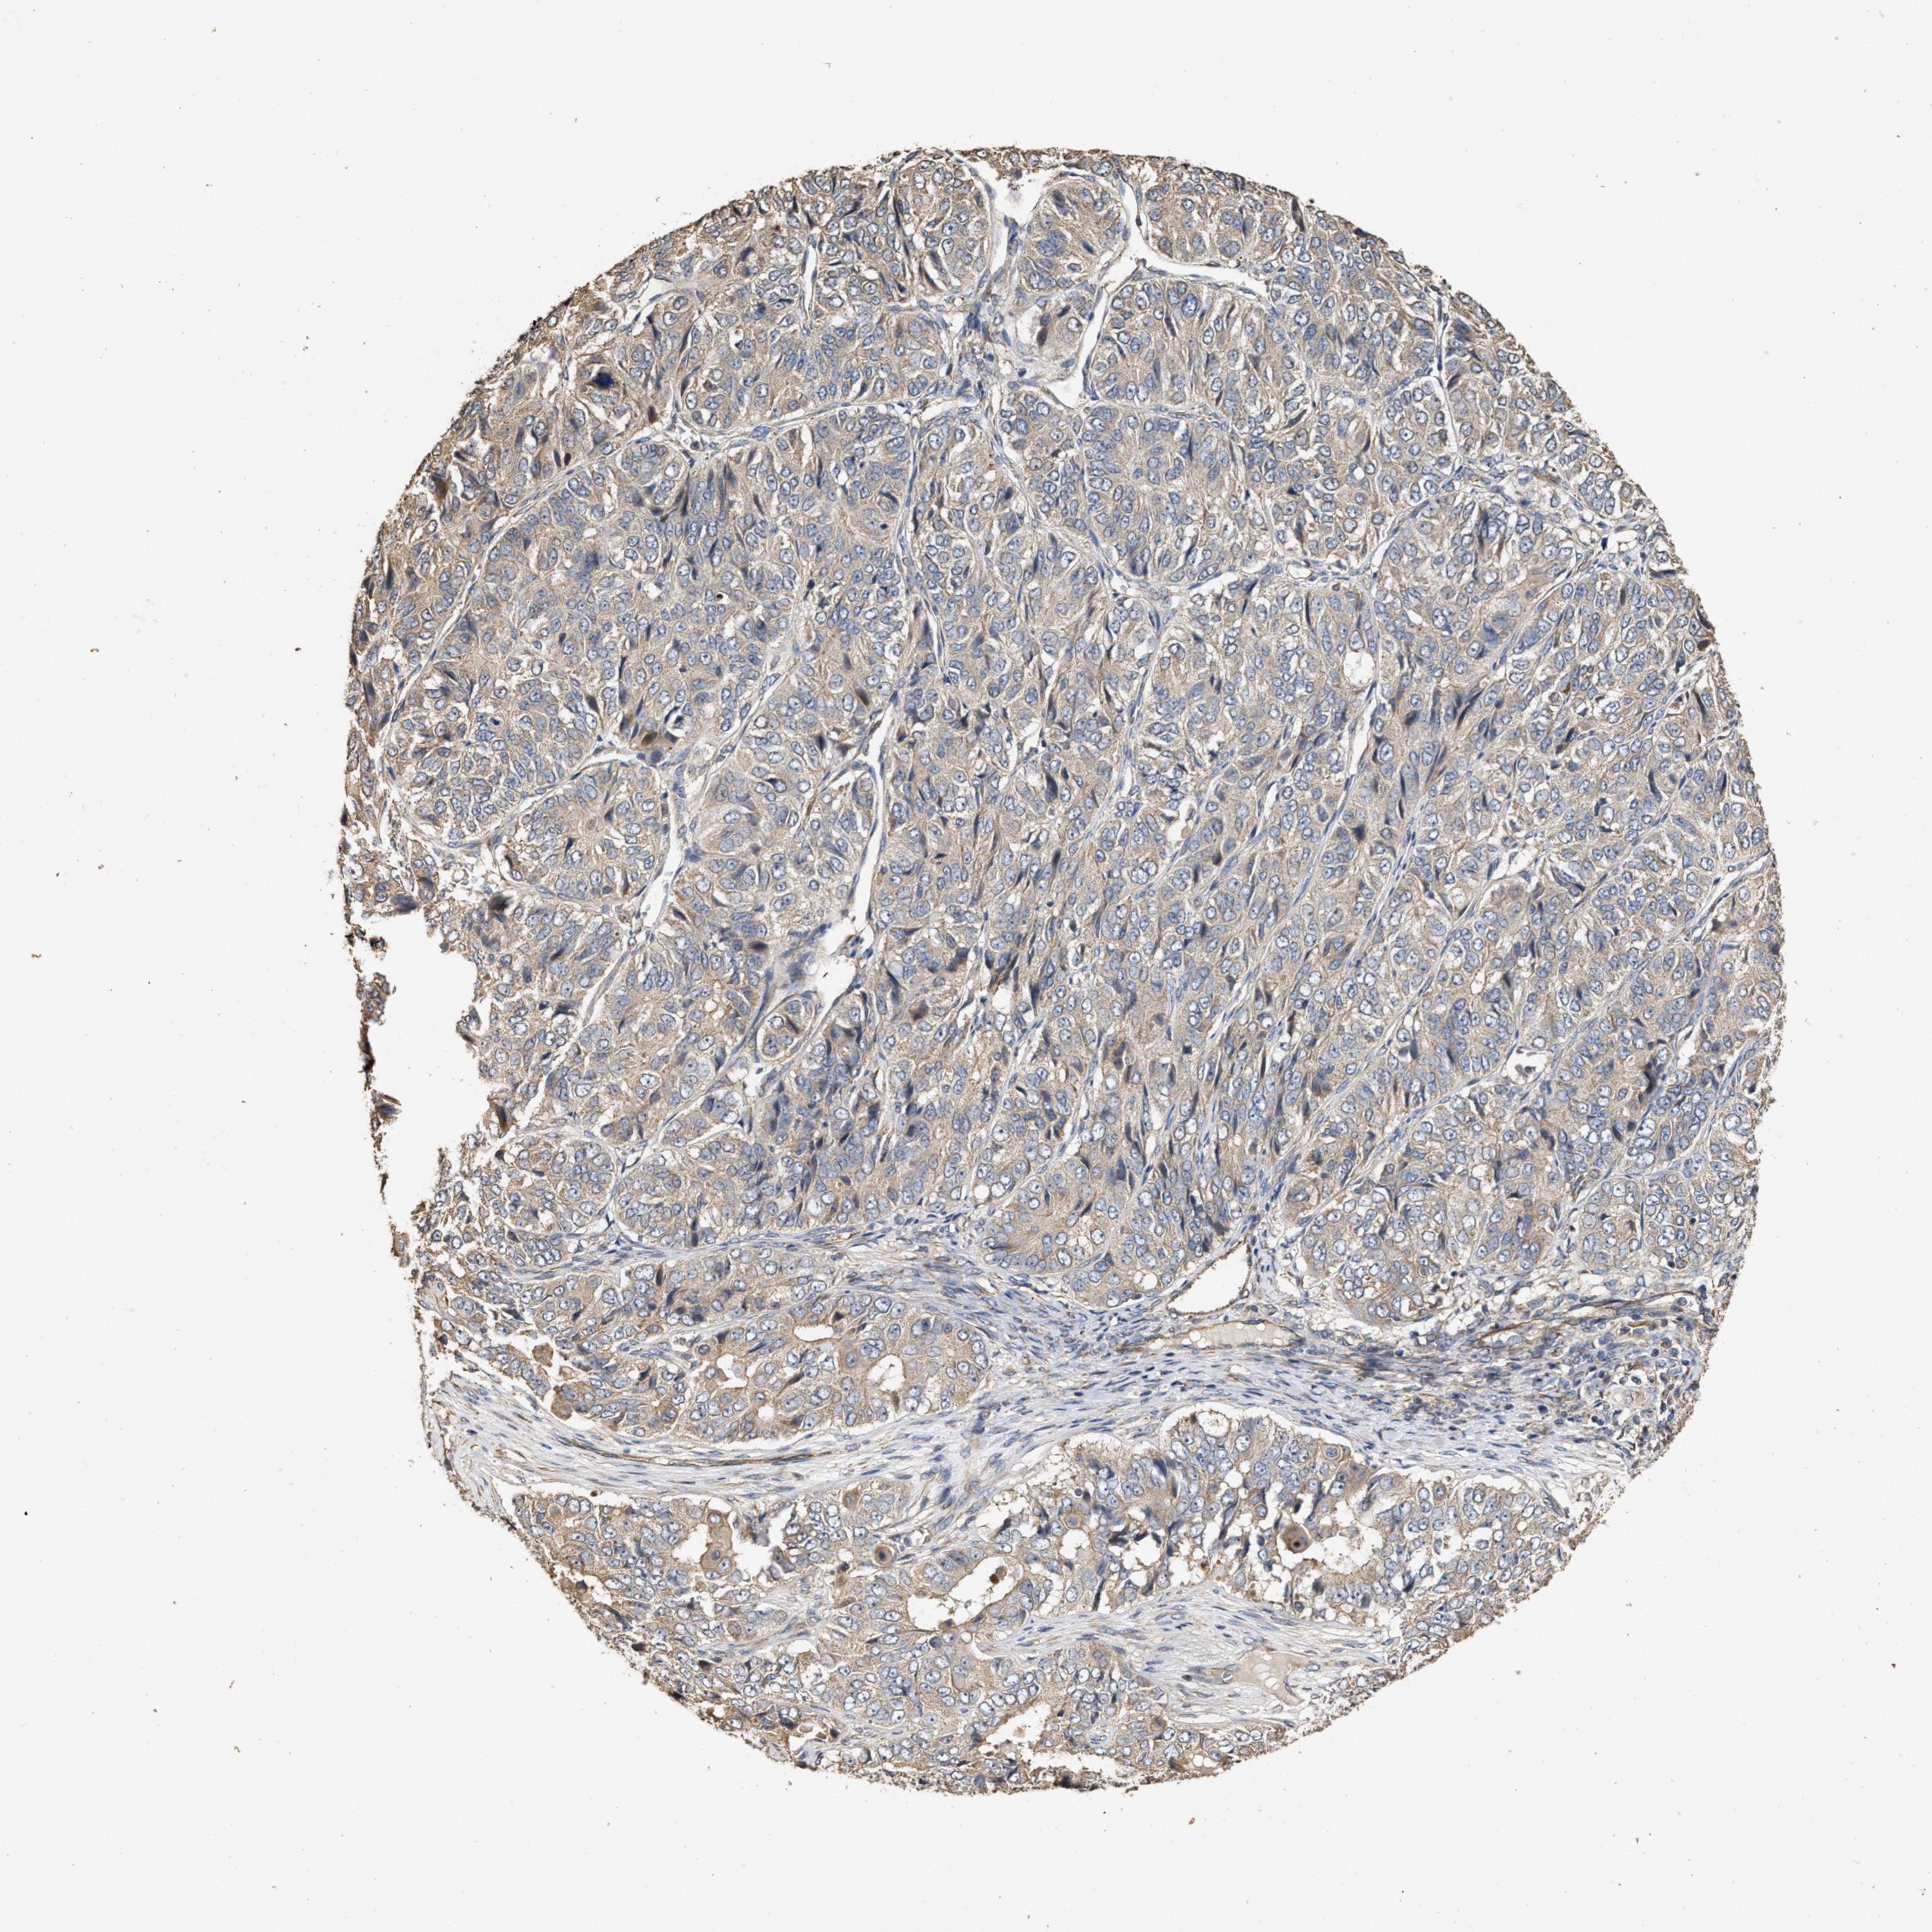

OVARIAN CANCER - Protein expressioni

A mouse-over function shows sample information and annotation data. Click on an image to view it in a full screen mode. Samples can be filtered based on level of antibody staining by selecting one or several of the following categories: high, medium, low and not detected. The assay and annotation is described here.

Note that samples used for immunohistochemistry by the Human Protein Atlas do not correspond to samples in the TCGA dataset.

Antibody stainingi

Antibody staining in the annotated cell types in the current human tissue is reported as not detected, low, medium, or high, based on conventional immunohistochemistry profiling in selected tissues. This score is based on the combination of the staining intensity and fraction of stained cells.

Each image is clickable and will lead to virtual microscopy that enables deeper exploration of all samples and also displays staining intensity scores, fraction scores and subcellular localization as well as patient and tissue information for each sample.

Antibody HPA018127

Cystadenocarcinoma, serous, NOS